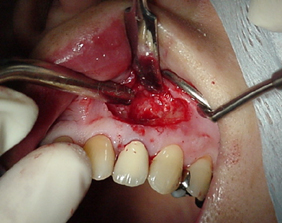

切開と術野の明示

セラミッククラウンが入っていたので切開線はpalchの弧状切開にしました。